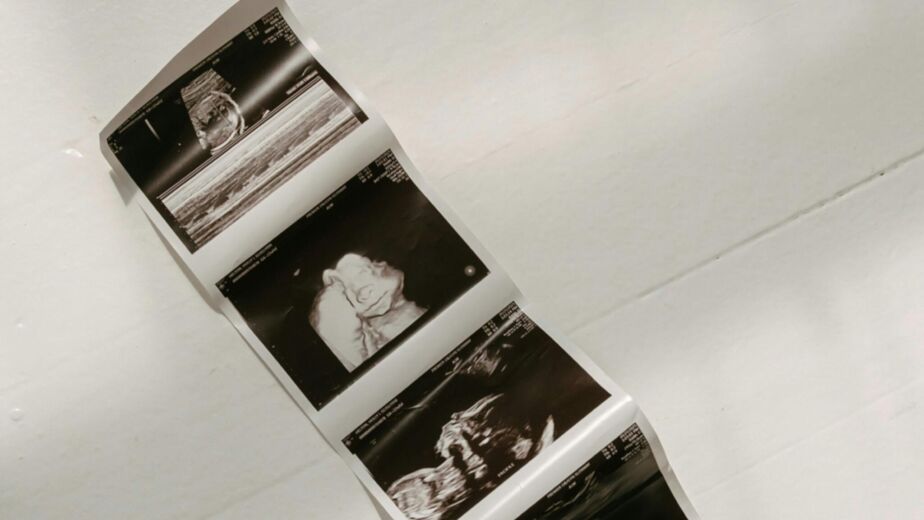

Adds a new dimension to the images, creating a three-dimensional view of the baby.

Offers a more detailed visualization of the baby’s features, allowing parents to see facial expressions and finer details.

4D Ultrasound

Takes 3D ultrasound a step further by providing a real-time video effect.

Captures the baby’s movements, offering an incredible, dynamic view of your little one in the womb.